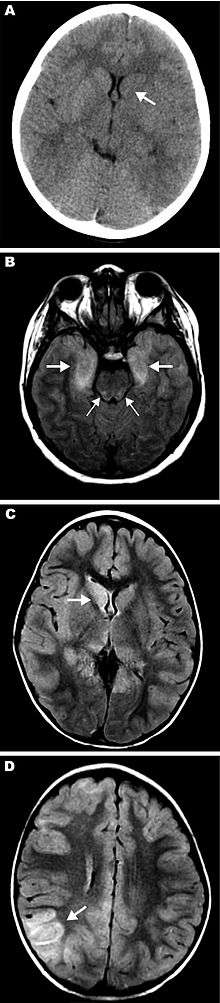

Magnetic resonance images (MRIs) and computed tomography (CT) neuroradiographs showing lesions in brains of 3 children with eastern equine encephalitis. A) Results of noncontrast CT scan of the brain of patient 12 on hospital day 2; the neuroradiograph shows subtle hypoattenuation of the left caudate head (arrow) and diencephalic region. B) Axial fluid attenuated inversion recovery (FLAIR) image from brain MRI scan of patient 14 on hospital day 2; the image shows abnormal T2 hyperintense regions of the bimesial temporal regions (thick arrows) with accompanying abnormal T2 hyperintense regions of the dorsal pontomesencephalic regions (thin arrows). C, D) FLAIR images from brain MRI scan of patient 15 on hospital day 3. C) Abnormal T2 hyperintense caudate and thalamic nuclei, most prominent on the right (arrow). D) Abnormal T2 hyperintense regions are most prominent in the right parietotemporal gray matter (arrow) and subcortical white matter but are also seen scattered throughout.